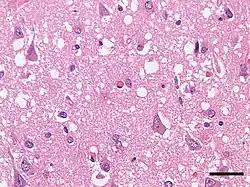

Micrograph showing spongiform degeneration (vacuoles that appear as holes in tissue sections) in the cerebral cortex of a patient who had died of Creutzfeldt–Jakob disease. H&E stain, scale bar = 30 microns (0.03 mm).

Prion diseases are marked by mental and physical deterioration that worsens over time.[5][6] A defining pathologic characteristic of prion diseases is the appearance of small vacuoles in various parts of the central nervous system that create a sponge-like appearance when brain tissue obtained at autopsy is examined under a microscope.[2][3] Other changes in affected regions include the buildup of PrPSc, gliosis, and the loss of neurons.[7]